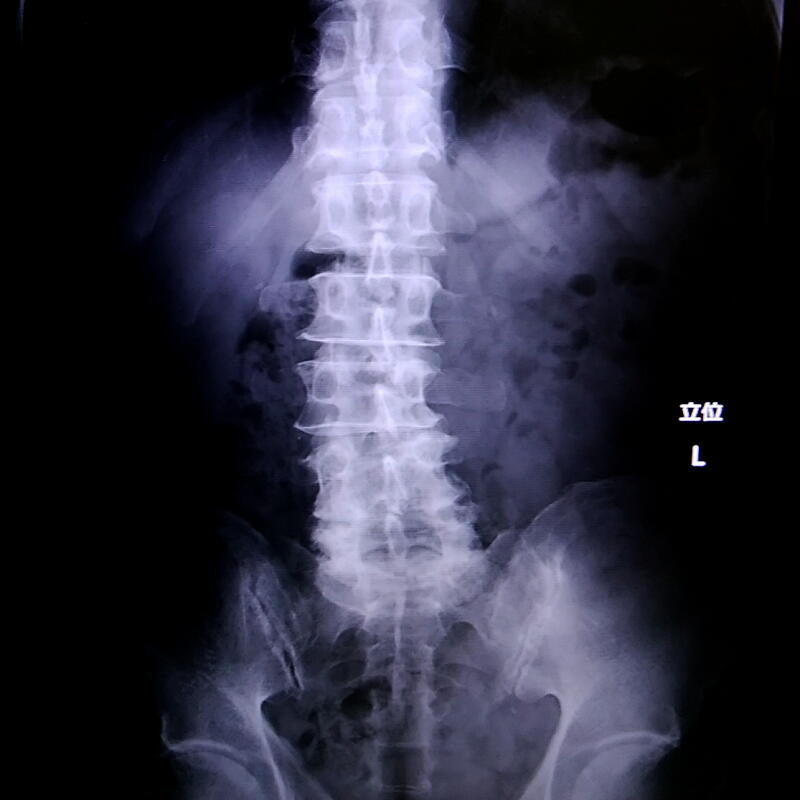

そしてレントゲンを撮った結果「腰椎変形症」という診断が下された。

加齢に伴う腰痛の多くは「腰椎すべり症」と言って腰椎が前後方向にずれるらしいのだけど、私の場合横方向にずれてしまっている。